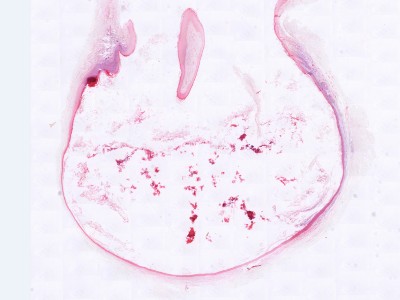

Histologie epidermoid cyste Histologie epidermoid cyste

ingescande coupe (zoom) ingescande coupe (zoom)

Bron hoge resolutie PA-foto's: Kevin Kwee en Afdeling Pathologie MUMC. Klik op de afbeelding om in te zoomen.